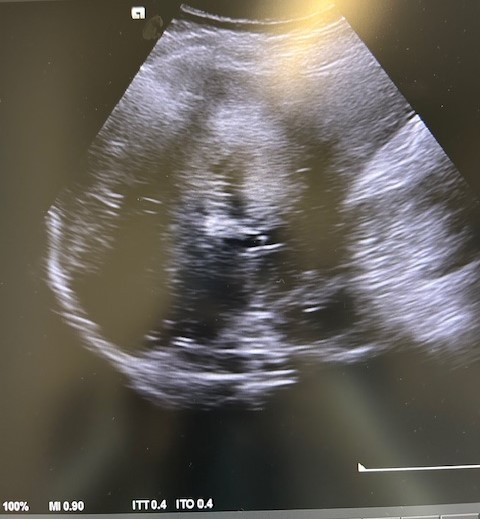

En la ecografía podemos apreciar hepatomegalia > 16 cm con múltiples imágenes en su interior hiperecogénicas sugestivas de LOE. No otros hallazgos a destacar.

El paciente fue valorado en Consultas Externas confirmando el diagnóstico. Se realiza ecografía abdominal con hallazgos de múltiples nódulos hepáticos de entre 12-35mm. En la colonoscopia, neoplasia circunferencial con aumento de consistencia, áreas ulceradas y necrosis, con estenosis incompleta, siendo compatible con adenocarcinoma de sigma.